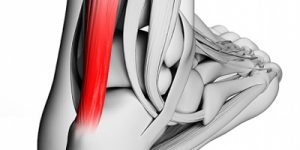

Rotura tendón de Aquiles

Rotura tendón de Aquiles La rotura del tendón de Aquiles sucede en cualquier rango de ...